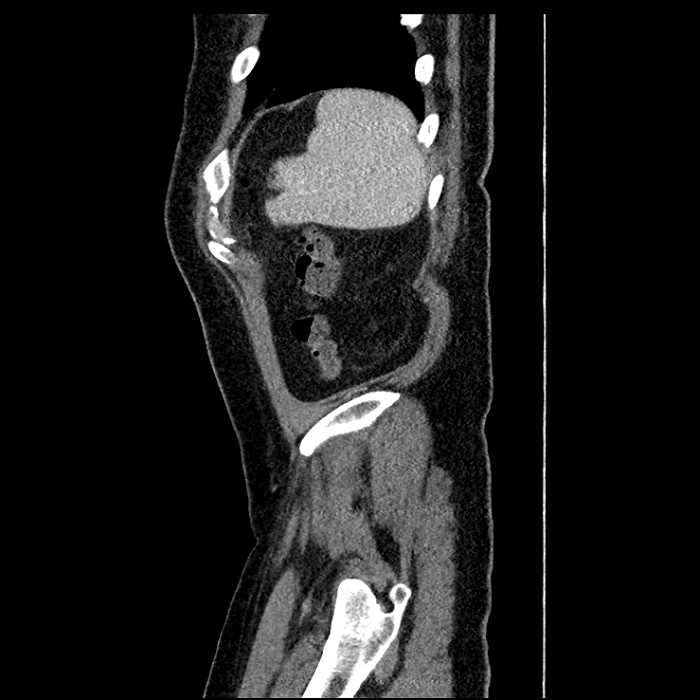

Age: 63

Sex: Male

Indication: Abdominal pain

• Large fluid density structure in hepatic segments 7 and 8 measuring 10 x 7 x 7 cm with internal septation and circumferential ill-defined low density compatible with edema

• Peripherally enhancing subcapsular collections along the anterior margin of the left hepatic lobe measuring 3 x 1 cm and 2 x 1 cm

• Clearly marginated fluid density structure in segment 7 and several other scattered tiny hypodensities, which likely represent cysts

• Hepatic abscess

Acute sigmoid diverticulitis complicated by a small contained perforation and a large abscess in the right hepatic lobe. Additional small subcapsular abscesses along the anterior margin of the left hepatic lobe.

• The classic CT imaging appearance is a double target sign with internal low density surrounded by an internal enhancing rim (capsule) and a low density external rim (edema)

• Abscesses may be unilocular or multilocular

Hepatic abscess showing the double target sign with low density internally surrounded by a thin inner enhancing rim (red arrow) and ill-defined outer low density rim (yellow arrow). Blue arrow indicates an internal septation. Red arrows: additional smaller subcapsular abscesses. Red arrow: focal contained perforation associated with diverticulitis.